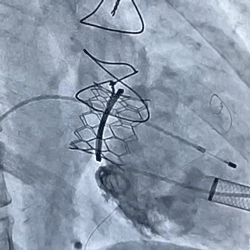

术前经详尽影像学重建和评估,CT重建测量成形环内径、左室流出道面积,查阅国外经验确定球扩式环中瓣植入最佳位置,并使用球扩式“环中瓣”进行了实物球扩与锚定等体外测试。考虑到之前经房间隔入路行瓣膜成形术,房间隔瘢痕严重,最终采用经心尖途径二尖瓣位植入27号Renato球扩瓣。手术顺利,主要操作时间不到半小时。最终环中瓣植入位置理想,锚定稳固,功能表现出色,术后即刻TEE测二尖瓣峰值流速1.4m/s,平均跨瓣压差2.7mmHg,左室流出道压差正常。TEE及DSA观察仅有轻微瓣周漏,无中央反流。患者术后恢复理想,临床症状明显缓解,已于术后一周内顺利出院。

环中瓣球扩释放 环中瓣植入后左室造影